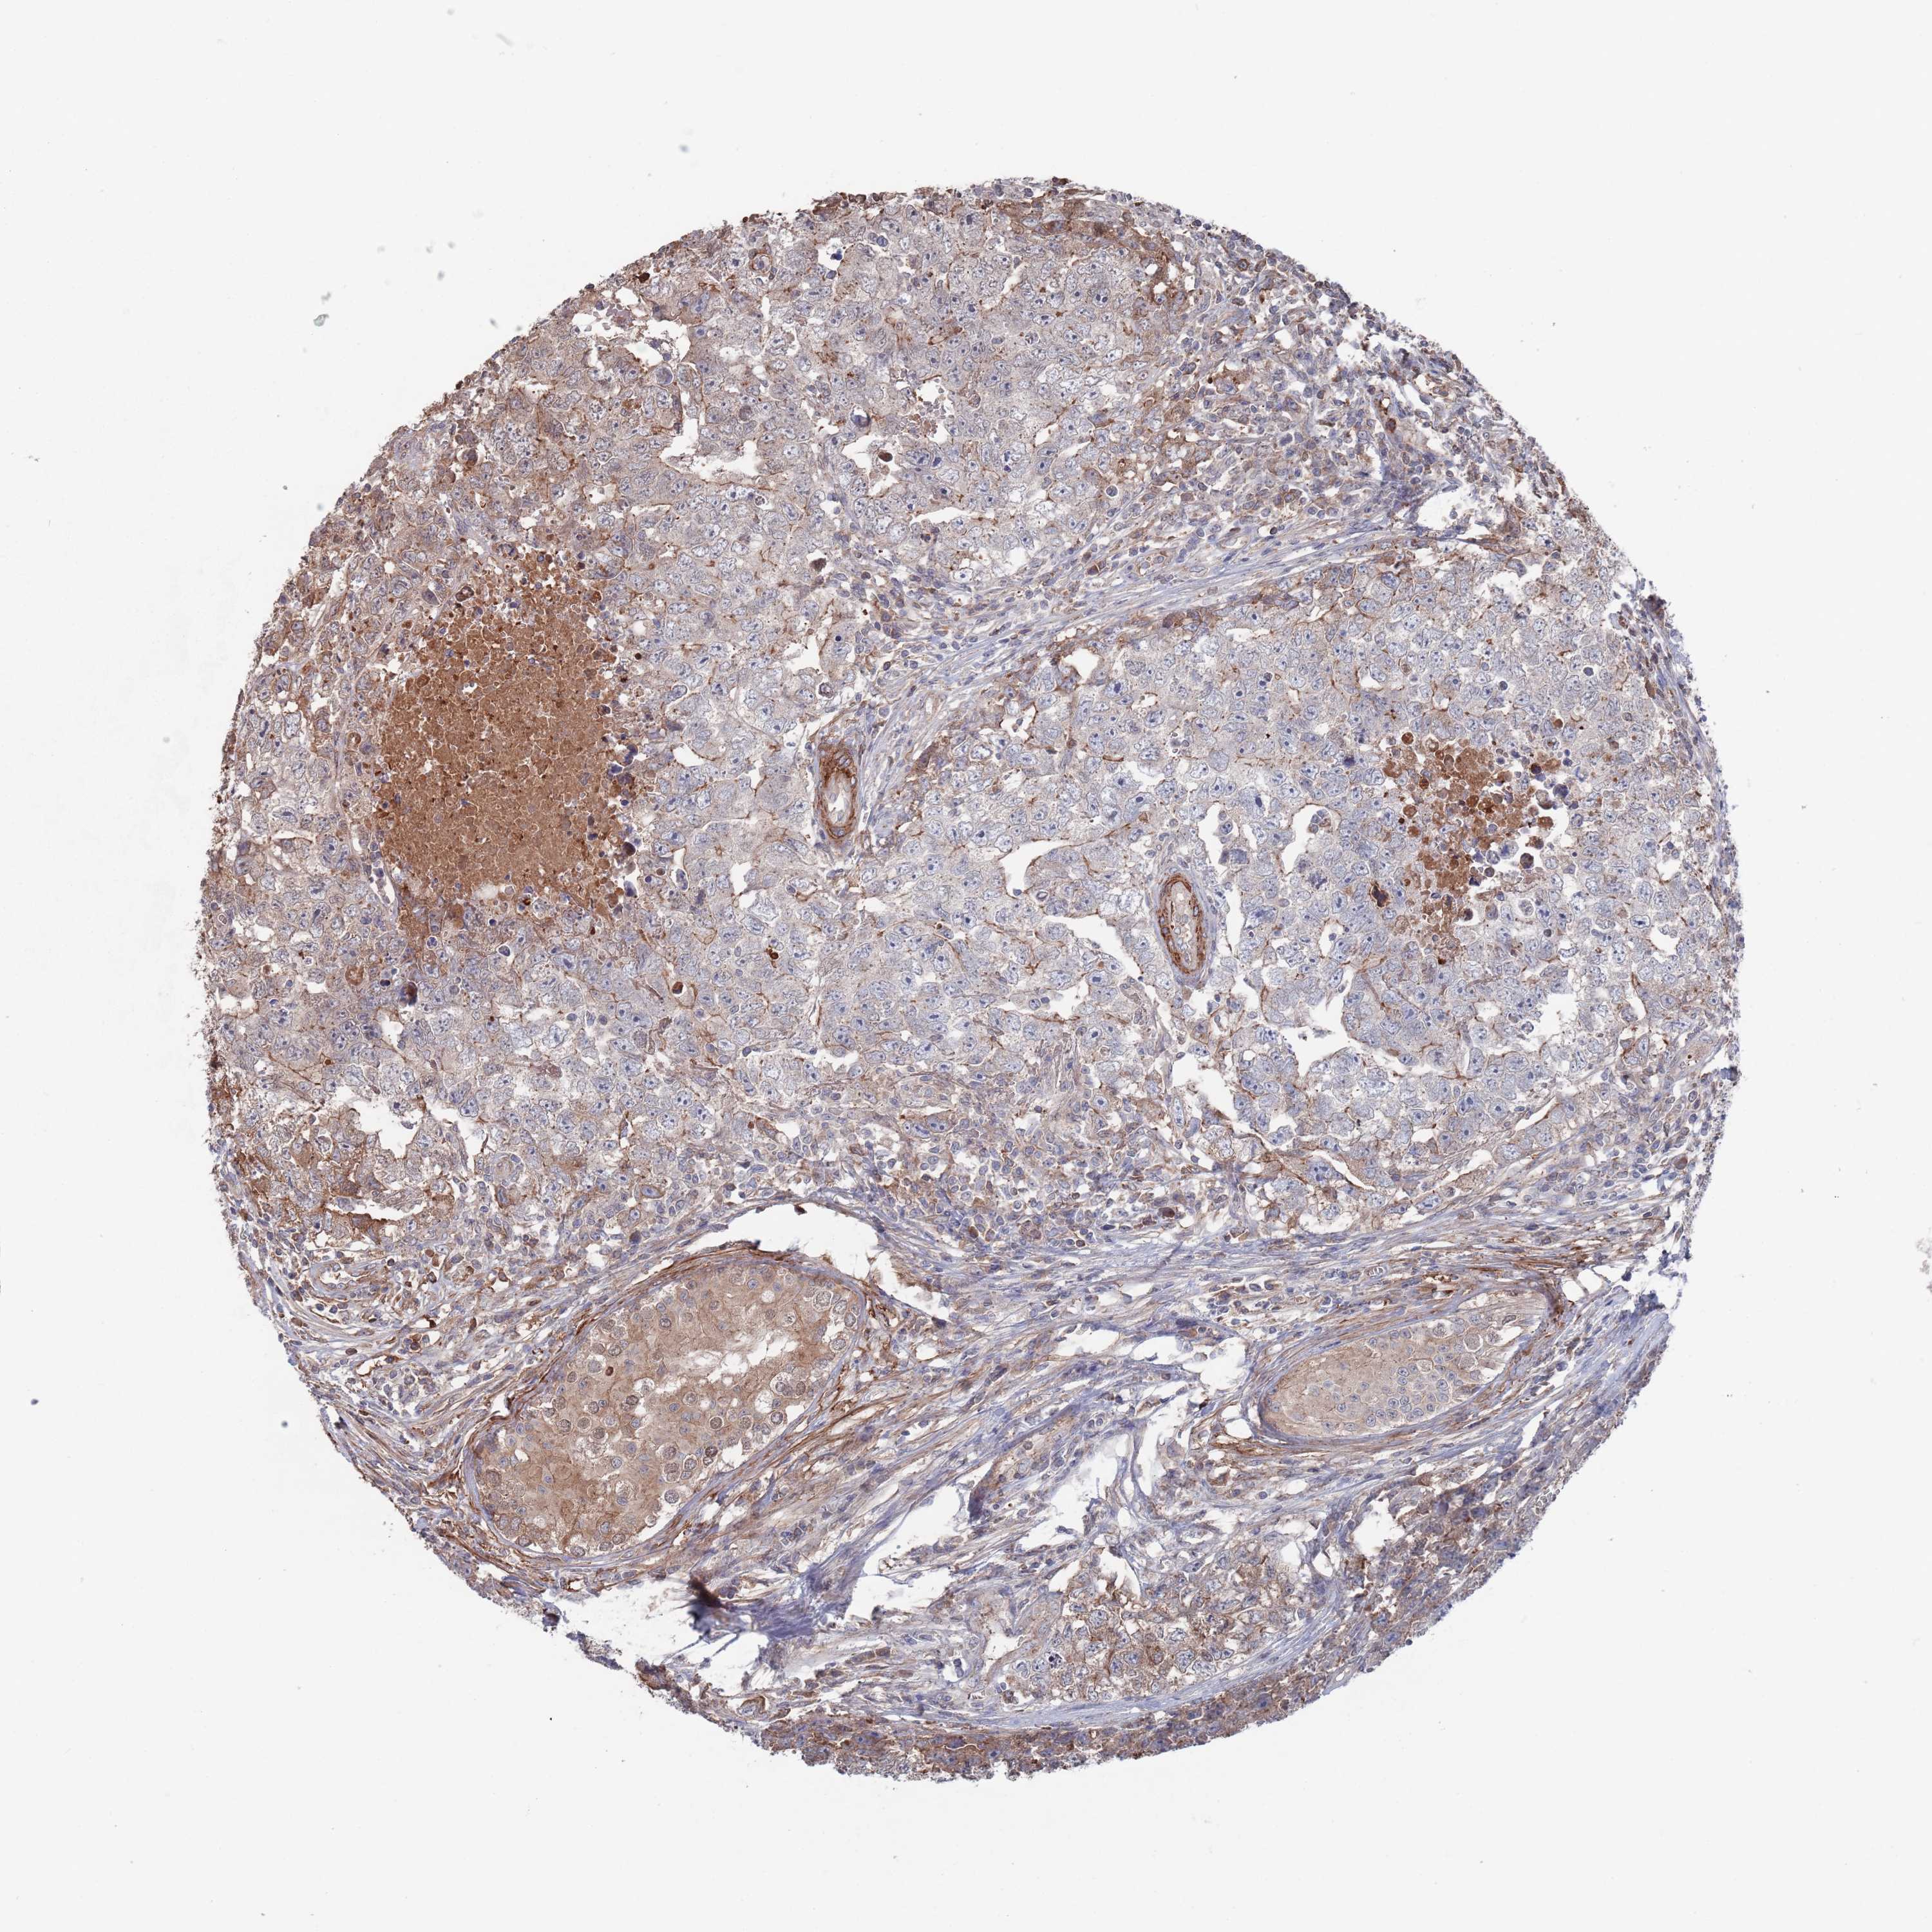

TESTIS CANCER - Protein expressioni

A mouse-over function shows sample information and annotation data. Click on an image to view it in a full screen mode. Samples can be filtered based on level of antibody staining by selecting one or several of the following categories: high, medium, low and not detected. The assay and annotation is described here.

Note that samples used for immunohistochemistry by the Human Protein Atlas do not correspond to samples in the TCGA dataset.

Antibody stainingi

Antibody staining in the annotated cell types in the current human tissue is reported as not detected, low, medium, or high, based on conventional immunohistochemistry profiling in selected tissues. This score is based on the combination of the staining intensity and fraction of stained cells.

Each image is clickable and will lead to virtual microscopy that enables deeper exploration of all samples and also displays staining intensity scores, fraction scores and subcellular localization as well as patient and tissue information for each sample.

Antibody HPA042978

Antibody HPA048473

Staining

High

Medium

Low

Not detected

Intensity

Strong

Moderate

Weak

Negative

Quantity

>75%

75%-25%

<25%

None

Location

Nuclear

Cytoplasmic/membranous

Cytoplasmic/membranous,nuclear

Carcinoma, Embryonal, NOS

Seminoma, NOS